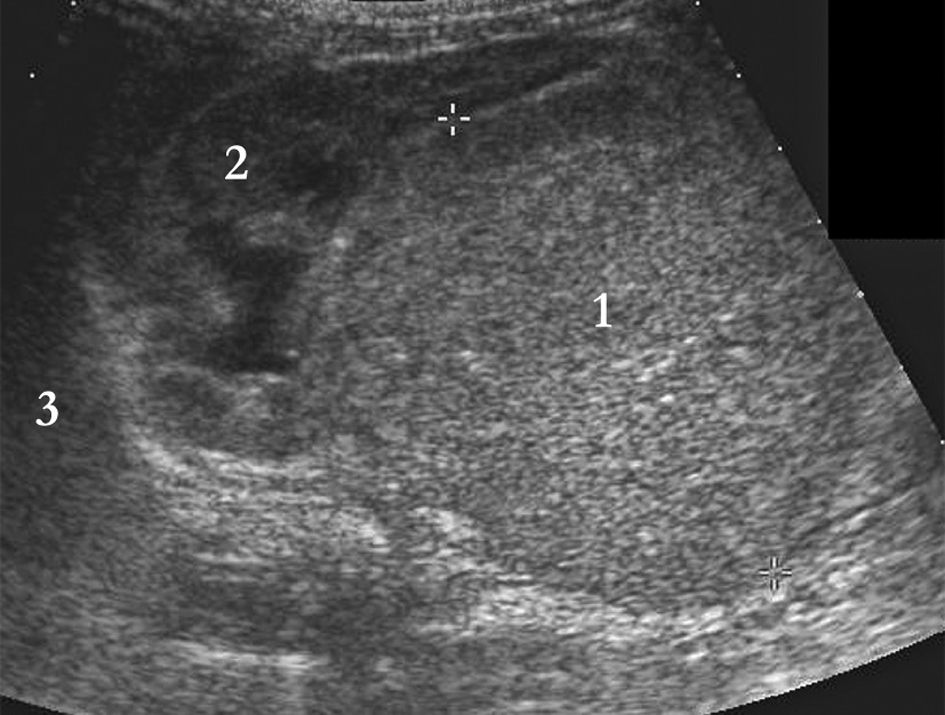

Devant une masse abdominale, l’échographie est l’examen de première intention. Elle permet de déterminer l’organe dont dépend la tumeur et participe au bilan d’extension de la lésion (figures 105.1 et 105.2).

Fig. 105.2 Coupe longitudinale sur le flanc droit mettant en évidence un neuroblastome avec injection de produit de contraste.

La masse (1) est homogène, d’échostructure tissulaire, et refoule le rein droit normal (2). Un liséré hyperéchogène sépare les deux. Le foie (3) est refoulé vers le haut.

Source : CERF, CNEBMN, 2022.